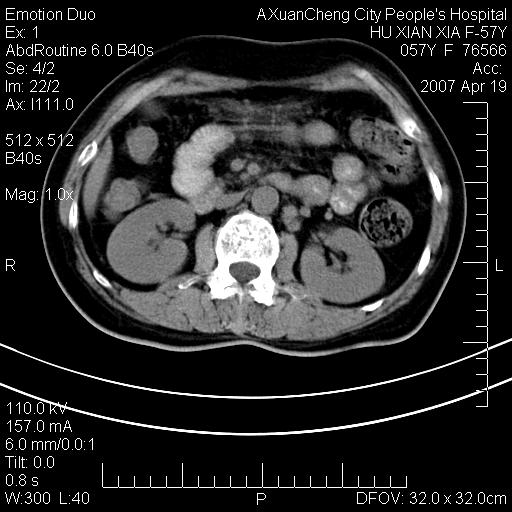

双侧肾上腺及腹膜后淋巴结增大,考虑转移,建议查原发灶.

双侧肾上腺增大,有分叶,密度均匀,考虑转移建议查原发灶

1.双侧肾上腺占位,转移首先考虑。

双侧肾上腺及腹膜后淋巴结增大,考虑转移,肺转移?

双侧肾上腺及腹膜后淋巴结增大,结合胸片提示肺部占位,考虑肺癌双侧肾上腺及腹膜后淋巴结转移.